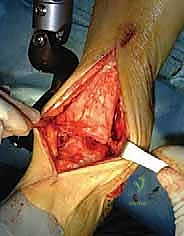

3. الشق الجراحي والوصول للمفصل

يقوم الدكتور هطيف بعمل شق جراحي أمامي (Anterior Approach) بعناية فائقة لتجنب الأوتار والأعصاب والأوعية الدموية الرئيسية. باستخدام تقنيات الجراحة المجهرية، يتم إبعاد الأنسجة الرخوة بلطف للوصول إلى المفصل التالف.

4. تحضير العظام ودمج القصبة والشظية

هذه هي الخطوة الأكثر حيوية في نظام Agility. يتم إزالة الغضروف التالف والزوائد العظمية. ثم يتم تحضير السطح السفلي لعظمة القصبة (Tibia) والسطح العلوي لعظمة الكاحل (Talus) باستخدام أدوات قطع دقيقة لضمان ملاءمة مثالية للمفصل الصناعي. بالتوازي، يتم تجهيز المسافة بين القصبة والشظية ووضع طعوم عظمية (Bone Grafts) لضمان التحام العظمتين معاً، مما يشكل قاعدة صلبة للمكون العلوي.